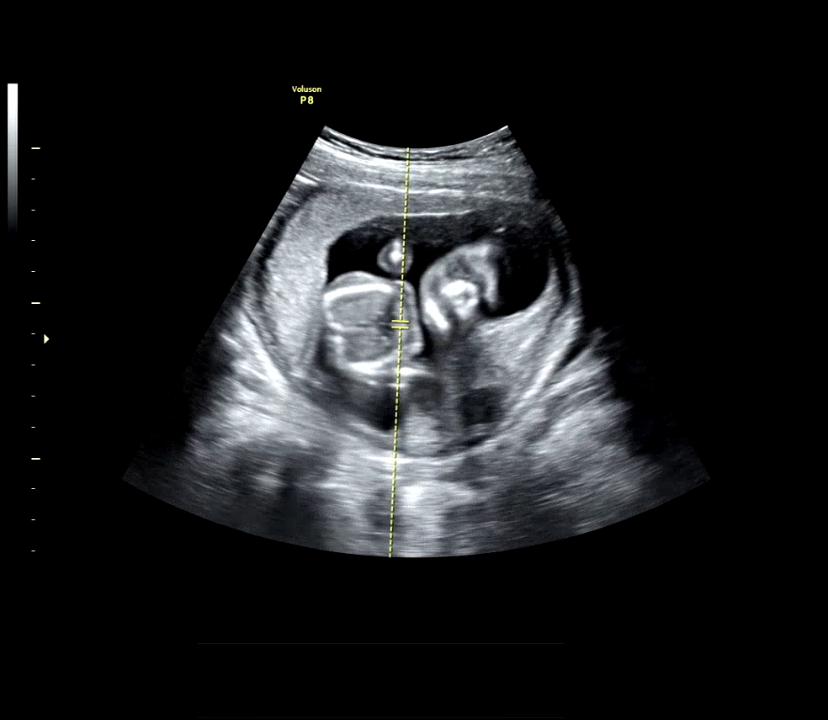

12주차 / 16주차 / 24주차(머리가 낑겨서 좀 좁아보임)